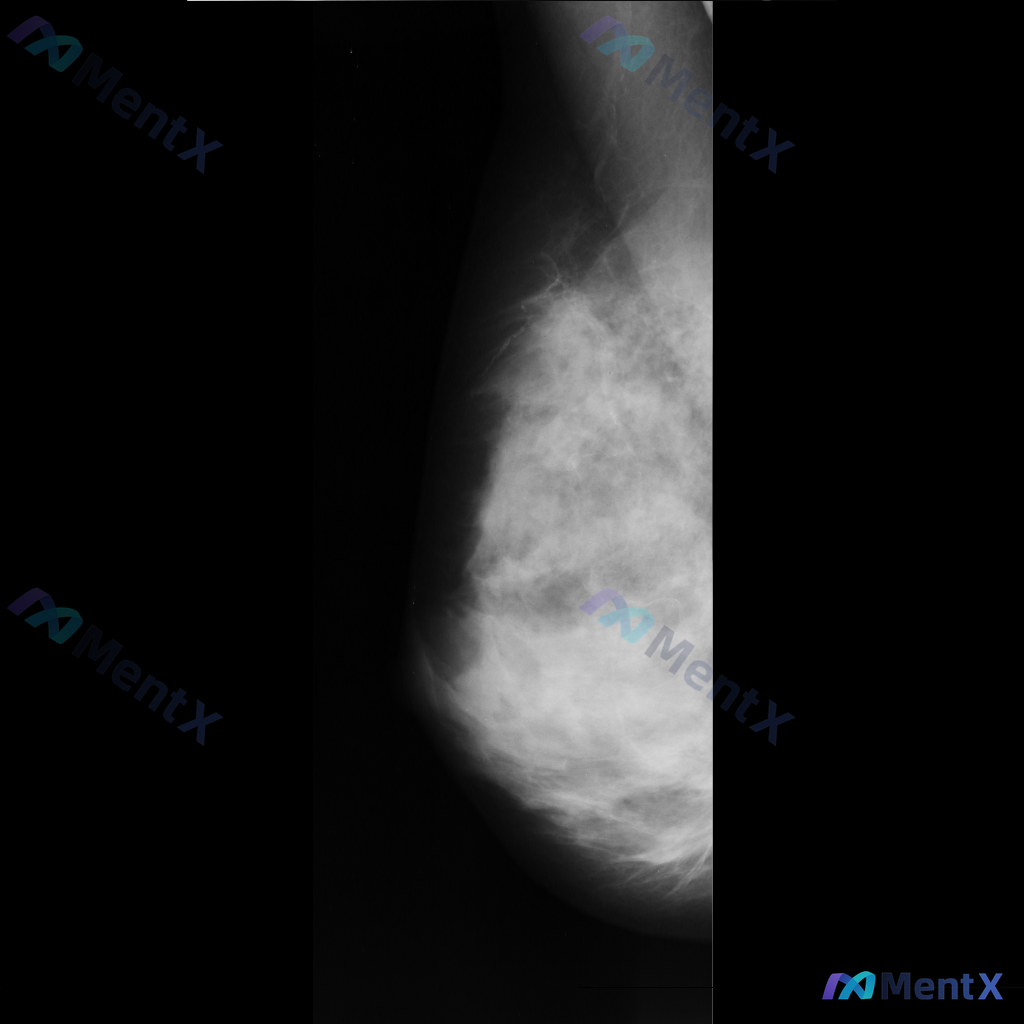

整理到一组乳腺钼靶影像的资料,分享给大家讨论: - 背景:不均匀致密型乳腺(BI-RADS C类) - 主要异常: 1. 乳腺下象限靠近乳头乳晕区,见两个大小不一的圆形/卵圆形高密度影,还有一个较小的类圆形高密度影,密度高于周围腺体,边缘相对清晰但略显模糊; 2. 上述高密度影周围的乳腺下象限,腺体...

整理到一张乳腺钼靶的读片资料,想和大家一起讨论一下。 图像里能看到两处比较明确的异常: - 乳腺中下部有一个不规则、毛刺状的高密度肿块,周围还有结构扭曲的表现 - 乳腺上部还有一个类圆形的高密度肿块,形态相对规则一些 背景是不均匀致密型的乳腺组织。 单看这组图像表现,大家会优先往哪个方向考虑?

整理到一组乳腺钼靶的影像资料,大家先一起看看: 影像表现: - 病灶位于乳腺上中部(大致外上象限)可见一局限性高密度肿块影 - 形态不规则,边缘有毛刺状改变 - 周围腺体结构有扭曲、牵拉征象 - 肿块内部或附近可见点状钙化,部分呈簇状分布 目前只有这组钼靶表现,大家先不补充更多临床信息的话,大家更倾...

整理到一张乳腺钼靶影像资料,主要表现如下: - 乳腺内可见一个较大的肿块,形态不规则,边界部分模糊、呈毛刺状,密度较高,同时伴有明显的结构扭曲; - 另外还存在一枚较小的圆形、边界相对清晰的高密度结节。 想和大家讨论一下:单看目前这组影像表现,你会更倾向哪一种判断方向?